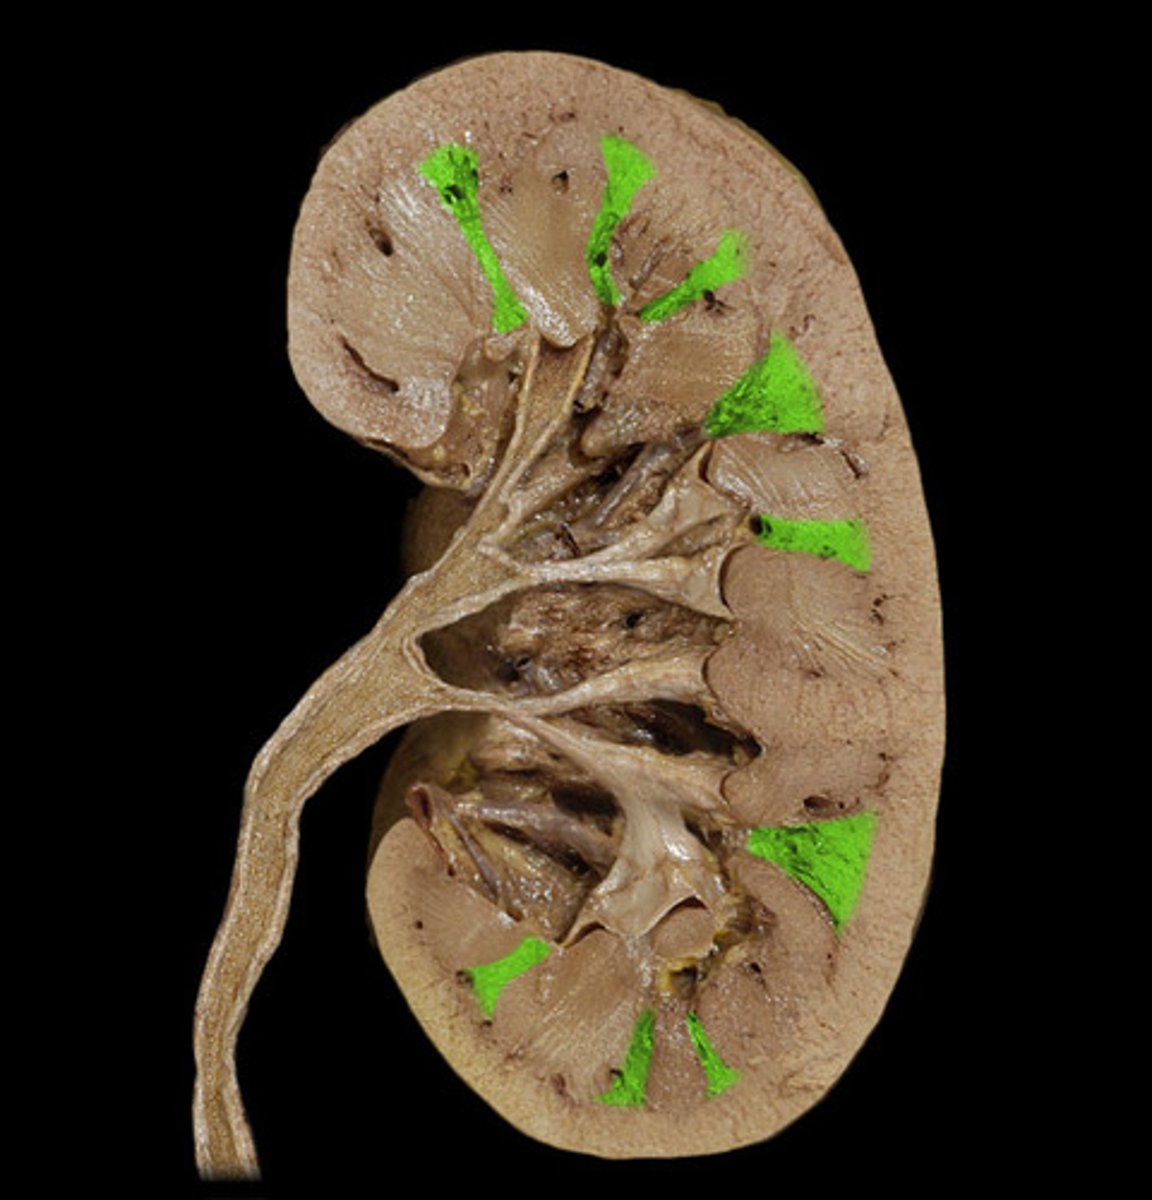

Renal columns

Renal medulla includes what?

Renal pyramids

Renal papillae